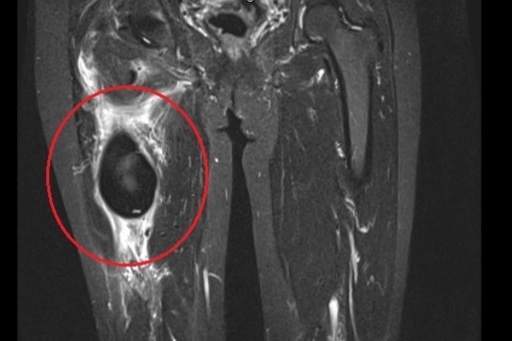

Người đàn ông 32 tuổi có thể sớm đi lại được sau ca đại phẫu thay thế khối khung chậu - khớp háng bằng titanium.

Sau thời gian bệnh nhân tự điều trị tại nhà, khối u gây ra cảm giác đau tăng dần, ảnh hưởng nghiêm trọng tới sinh hoạt hàng ngày.